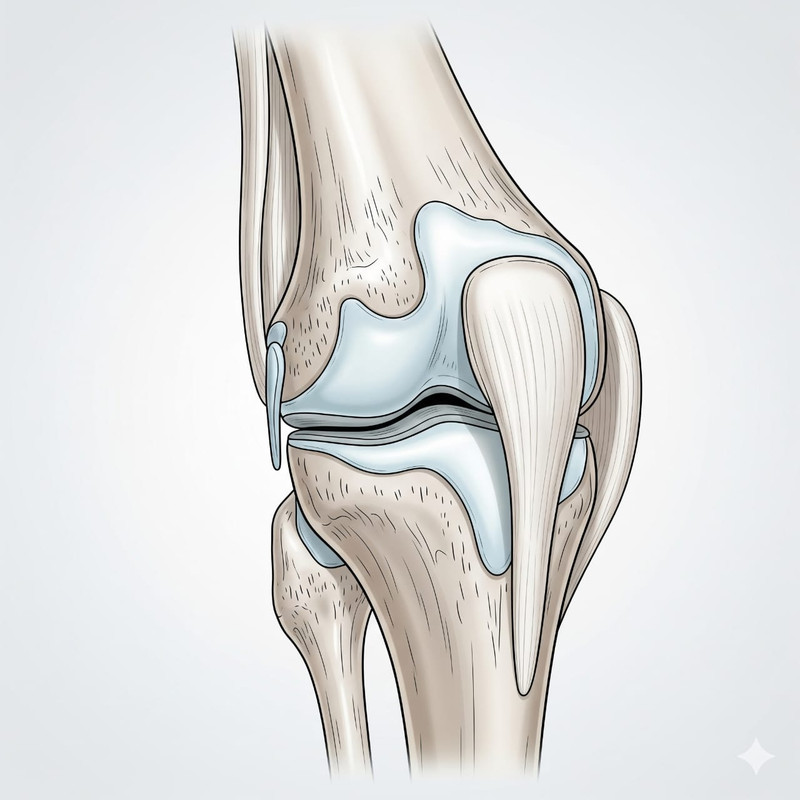

We also provide: Spondylitis (Kamar Dard), Arthritis (Ghutne ka Dard), Gastric problems, Gathia, Body pain massage, Piles, and handmade traditional medicines.